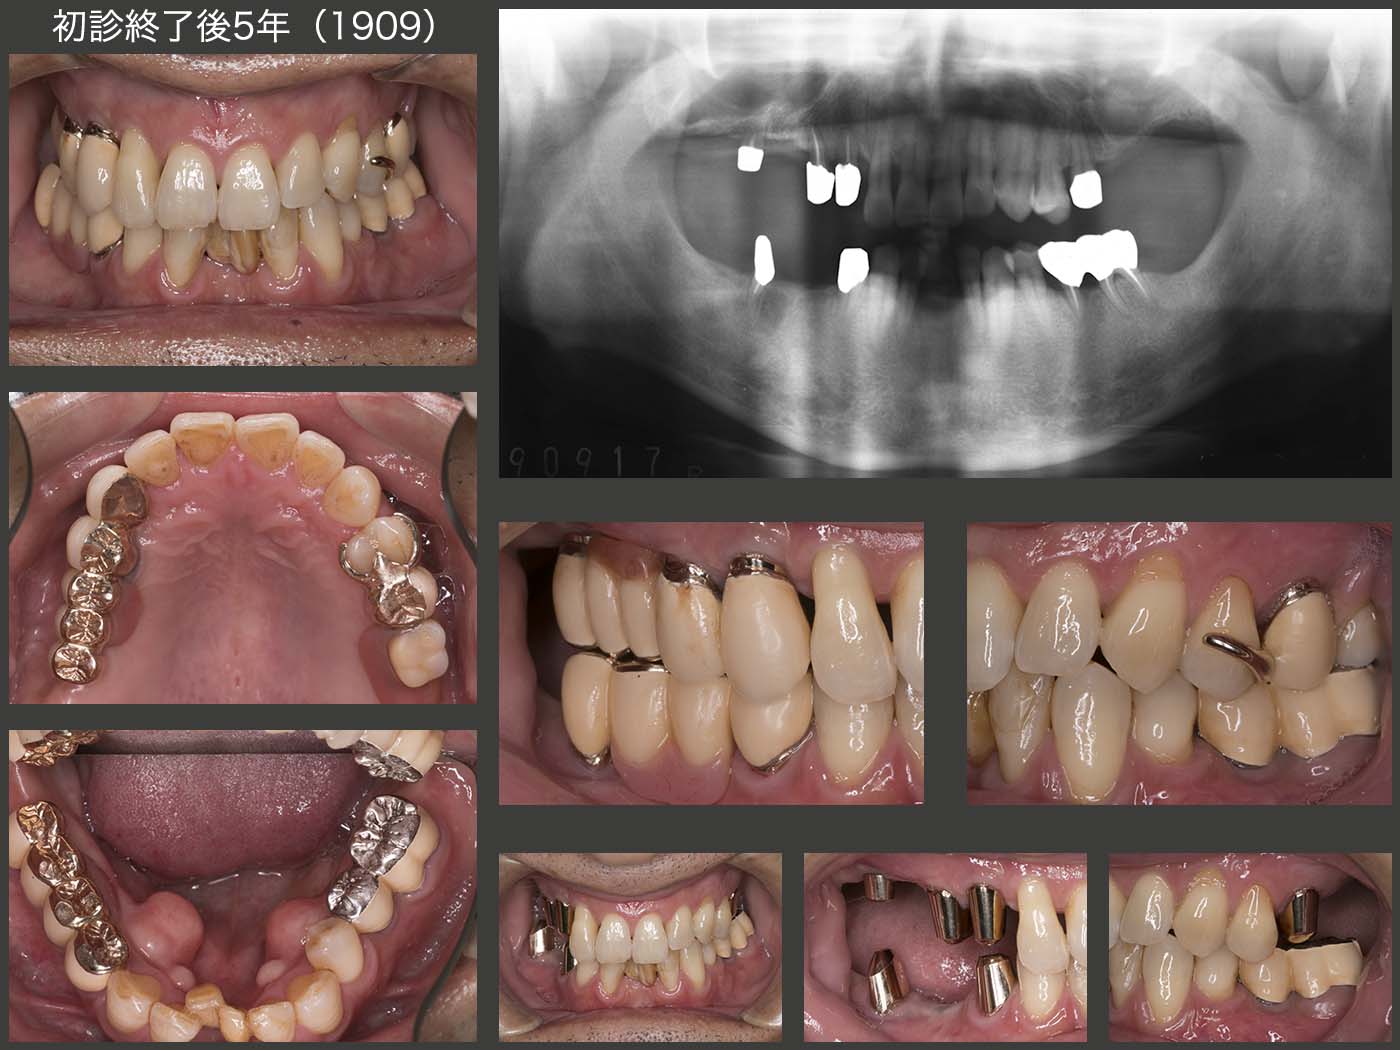

4.重度歯周病にコーヌス義歯で対応(2)

2008年7月初診,58歳男性.他院で上顎はすべて抜歯し,総義歯にするという説明を受けた.何とか歯を残せないか?とのことで当院を受診した.

まず,9月に保存不可能な右上5,6を抜歯し,即時義歯を装着した.(スライド写真は12月の状態.大連結装置の違和感が強くあまり使用していない.) 歯周ポケットは,右上2〜4および左上1は最深部で8〜10mm存在した.また1日1箱のたばこを吸っていた.まず,歯周ポケットの深い左上1,右上2を抜髄し,左上1,右上2〜4の自然挺出を行った.左上1は約1年経過を観察したが,歯周ポケットが改善せず抜去した.右上1〜4は歯周外科処置を行った.左上2は形成量が多かったためか歯髄炎を起こし,やむを得ず抜髄した.

2011年2月,初診終了時の状態.左上4は,これも形成量が多かったためか,内冠セット後に歯髄炎を起こしたため抜髄した.最終的には,上顎の残存歯をすべて支台歯としたコーヌス義歯を装着した.コーヌス義歯にすることで,2次的に支台歯を連結固定でき,また残存歯の清掃および将来の変更に対応しやすくなった.

上顎にはコーヌス義歯,下顎にはクラスプ義歯を装着した.右下段に2016年9月,5年7ヵ月後の状態を示す.13年1月に左下5を歯根破折で失ったが,暫くこのまま経過観察していた.16年6月,右咬みのためか右下6に歯髄炎が生じ,2週間様子をみたが痛みが一向に治まらず仕方なく抜髄した.なお,左下5にも1本義歯を装着してもらった.

初診時,初診終了時,初診終了後5年7ヵ月のパノラマX線写真の比較.2016年9月時点の歯周ポケットは上顎の歯は5mm以下であるが,下顎の歯は,右下6および左下6に最大7mm認められた.総合的には順調に経過していると思えるが,最近,以前ほど口の中に関心がなくなってきているように見受けられる.この先が心配である.

その後,20年12月現在まで来院が途絶えている.